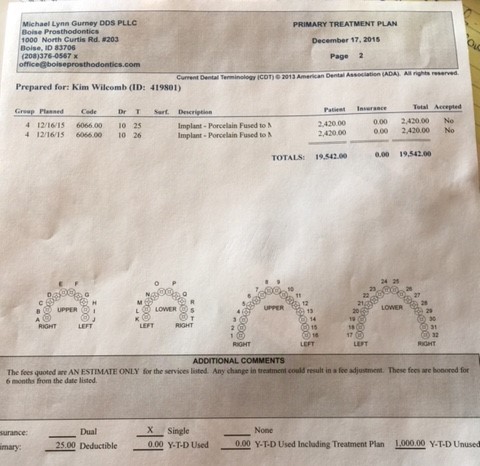

Once these two surgeries regarding the metal posts have occurred and recovery is successful, Kim will finally be given a new set of teeth on the left side. (Remember, this is without any knowledge of that second tumor of the right or the cost that will come with it). Although this seems far off in time at this point, the initial cost covers all surgeries and stages of the process regarding the porcelain implants. The current quote for the teeth and jaw replacement is $19,542.

Once these two surgeries regarding the metal posts have occurred and recovery is successful, Kim will finally be given a new set of teeth on the left side. (Remember, this is without any knowledge of that second tumor of the right or the cost that will come with it). Although this seems far off in time at this point, the initial cost covers all surgeries and stages of the process regarding the porcelain implants. The current quote for the teeth and jaw replacement is $19,542.